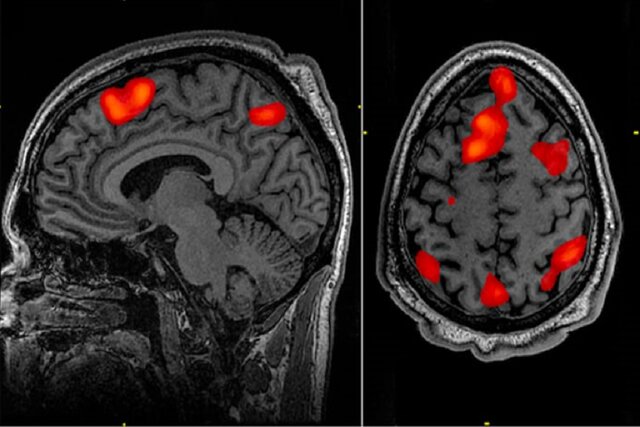

چندین پژوهش که طی سالهای اخیر انجام شدهاند، نتایج مشابهی را گزارش کردهاند. به نظر میرسد که بزرگسالان جوانتر، اطلاعات نامربوط را مهار میکنند؛ این در حالی است که به نظر میرسد بزرگسالان مسنتر آن را ذخیره میکنند. یافتههای تصویربرداری عصبی نیز نتایج مشابهی را ارائه میدهند.

دکتر "تارک آمر"(Tarek Amer)، پژوهشگر ارشد این پروژه گفت: بررسی فعالیت مغز نشان داد که افراد مسن برخلاف بزرگسالان جوان، هر دو دستهبندی تصویر مرتبط و نامرتبط را به خاطر میآورند. این نشان میدهد که سالمندان، این تصاویر را زمانی به خاطر میآوردند که قرار بود آنها را نادیده بگیرند و از این ایده پشتیبانی میکند که سالمندان، اطلاعات زیادی را پردازش و ذخیره میکنند.